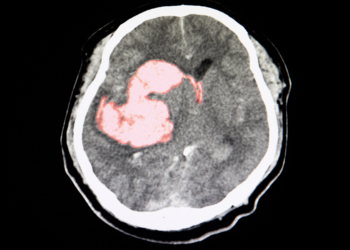

This video discusses blood pressure and heart-related health topics

for general awareness. It may help viewers understand cardiovascular